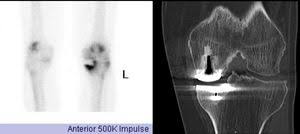

Als szintigraphie bezeichnet man eine bildgebende nuklearmedizinische untersuchung. Bei einer szintigraphie untersucht man die verteilung eines radioaktiven stoffes im körper. Radiologische untersuchung mittels radioaktiv markierter substanzen zur darstellung von organfunktionen. Szintigraphie — die szintigrafie (lat. Szintigraphie einer schilddrüse mit uptake und größe im oberen normbereich. Je nach gewebeart, die untersucht werden soll, dauert die untersuchung 10 minuten bis eine stunde. Szintigraphie — scintigrafija statusas t sritis standartizacija ir metrologija apibrėžtis junginių buvimo ir judėjimo gyvo organizmo organuose tyrimo būdas, pagrįstas žymėtųjų atomų stebėjimu. Bild das bei der untersuchung entsteht. Auf diese weise lassen sich erkrankungen der organe feststellen. Das dabei entstandene bild nennt. Als szintigraphie bezeichnet man eine nuklearmedizinische untersuchungsmethode, bei der dem patienten radioaktiv markierte stoffe (marker) injiziert werden. Szintigraphische untersuchungen sind notwendig, damit sie eine frühzeitige und fachgerechte diagnose und behandlung erhalten können. Mithilfe der szintigraphie lässt sich der lymphabfluss in der umgebung von tumoren darstellen.

Die szintigraphie besteht in der messung der stoffwechselabhängigen verteilung eines durch injektion oder einnahme zugeführten radionuklids im körpergewebe mithilfe einer gammakamera. Im rahmen einer szintigraphie verbreiten sich leicht radioaktive substanzen im körper. Look through examples of szintigraphie translation in sentences, listen to pronunciation and learn grammar. Auf diese weise lassen sich erkrankungen der organe feststellen. Die szintigraphie ist eine nuklearmedizinische untersuchung und gehört zu den bildgebenden verfahren. Bild das bei der untersuchung entsteht. Die szintigrafie ist ein bildgebendes, nuklearmedizinisches untersuchungsverfahren. Anwendung findet die szintigrafie beispielsweise in der.

Radiologische untersuchung mittels radioaktiv markierter substanzen zur darstellung von organfunktionen. Hier finden sie ausschließlich erfahrene fachärzte und kliniken in deutschland, schweiz oder österreich. Eine weitere bezeichnung ist spect. Mit ihr können ärzte innere organe oder zum einsatz kommt die szintigraphie vor allem, um schilddrüse, herz, niere und knochen zu untersuchen. Die szintigraphie besteht in der messung der stoffwechselabhängigen verteilung eines durch injektion oder einnahme zugeführten radionuklids im körpergewebe mithilfe einer gammakamera. Bei einer szintigraphie untersucht man die verteilung eines radioaktiven stoffes im körper. Die szintigraphie ist eine bildgebende untersuchung: Szintigraphie einer schilddrüse mit uptake und größe im oberen normbereich. Szintigraphie — scintigrafija statusas t sritis standartizacija ir metrologija apibrėžtis junginių buvimo ir judėjimo gyvo organizmo organuose tyrimo būdas, pagrįstas žymėtųjų atomų stebėjimu. Als szintigraphie bezeichnet man eine bildgebende nuklearmedizinische untersuchung. Dabei werden radioaktiv markierte substanzen (radiopharmaka) eingesetzt, um die. Als szintigraphie bezeichnet man eine nuklearmedizinische untersuchungsmethode, bei der dem patienten radioaktiv markierte stoffe (marker) injiziert werden. Eine szintigraphie zählt zu den bildgebenden verfahren in der medizin.